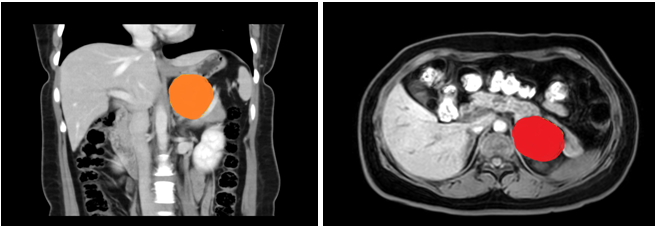

患者,女性,35岁,在三级片 上腹部CT增强示:左侧腹膜后囊性病变,支气管囊肿不除外;入院后上腹部MRI平扫+DWI+增强扫描+MRCP示:左侧肾上腺上方囊性病变,考虑来源腹膜后间隙,1)支气管源性囊肿2)淋巴管囊肿可能,建议复查。

在张煜副主任带领下,经过肝胆外科全科细致讨论,认为占位较大,位置靠后,微创难度大,需完善相关检查,精细术前准备。经过医护一体化管理,打消了患者的术前顾虑,在全麻下行腹腔镜下腹膜后囊性占位手术+广泛腹腔粘连松解术,手术顺利,术后病理结果为良性,患者术后一周内顺利出院。患者表示,术后经过了解,得知此例手术难度较大,目前恢复良好,特意送来锦旗表达感谢。